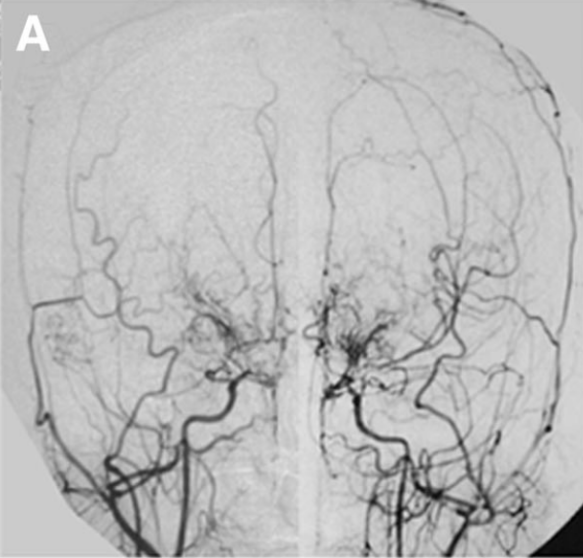

"切除率达到100%,动静脉畸形(AVM)无任何残留,我认为不会再复...

当时面临两种治疗方案:开颅手术彻底切除或创伤较小的伽马刀...